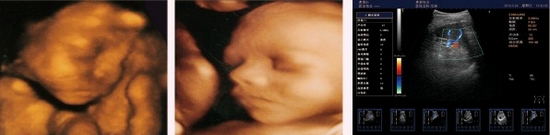

精確三維(3D)成像系統(tǒng)

全數(shù)字精確三維(3D)成像系統(tǒng),采用探頭陣元切割掃描,采集大量

精確地三維數(shù)據(jù),快速生產(chǎn)高分辨率、高清晰度的精確三維圖像,更

好的進(jìn)一步測(cè)量和診斷。